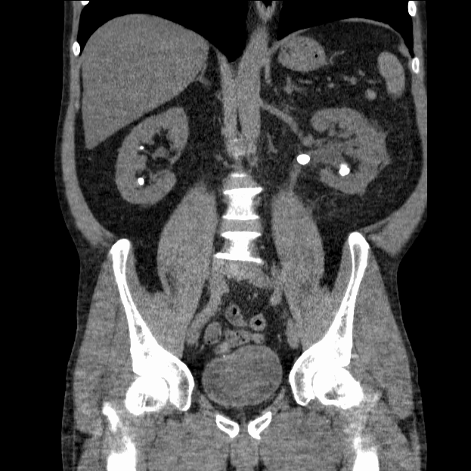

Stones which form in the kidney (intra-renal stones) can be problematic, or patients can be asymptomatic with stones detected on investigations for other reasons. Our patient had a small asymptomatic stone – the natural history of these is not well defined and the risk of a symptomatic episode or intervention is 10-25 per cent per annum. Intra-renal stones may cause pain, infections or obstruction. A patient may present acutely if a stone passes into the ureter (Figure 1), causing renal colic with or without haematuria, acute kidney injury, or features of urosepsis.

Management: He underwent an XR-KUB and stone profile bloods in urology clinic and was referred for a CT KUB. His CT showed a 1.5cm intra-renal right-sided non-obstructing stone. Following discussion of his management options, he underwent an elective flexible ureterorenoscopy with laser fragmentation of the stone with stent insertion. He was discharged home the same day.

A baseline x-ray kidneys, ureters, and bladder (KUB) is frequently performed in the urology outpatients. It carries a sensitivity and specificity of 44-77 per cent, and is easy to perform with low radiation exposure. If the stone is radiopaque, it is useful for follow-up imaging. However, a low-dose non-contrast CT KUB has become the standard for detailed evaluation of renal and ureteric stones as it will identify radio-opaque stones, and gives information on the anatomy and features of the stone such as its density and area.

A contrast-enhanced study gives further anatomical details and is helpful when intervention is being planned. Nuclear imaging such as a renogram is usually only performed if there is a concern about reduced kidney function or chronic obstruction – for example; if a kidney is small/atrophic, or in the setting of a staghorn stone.